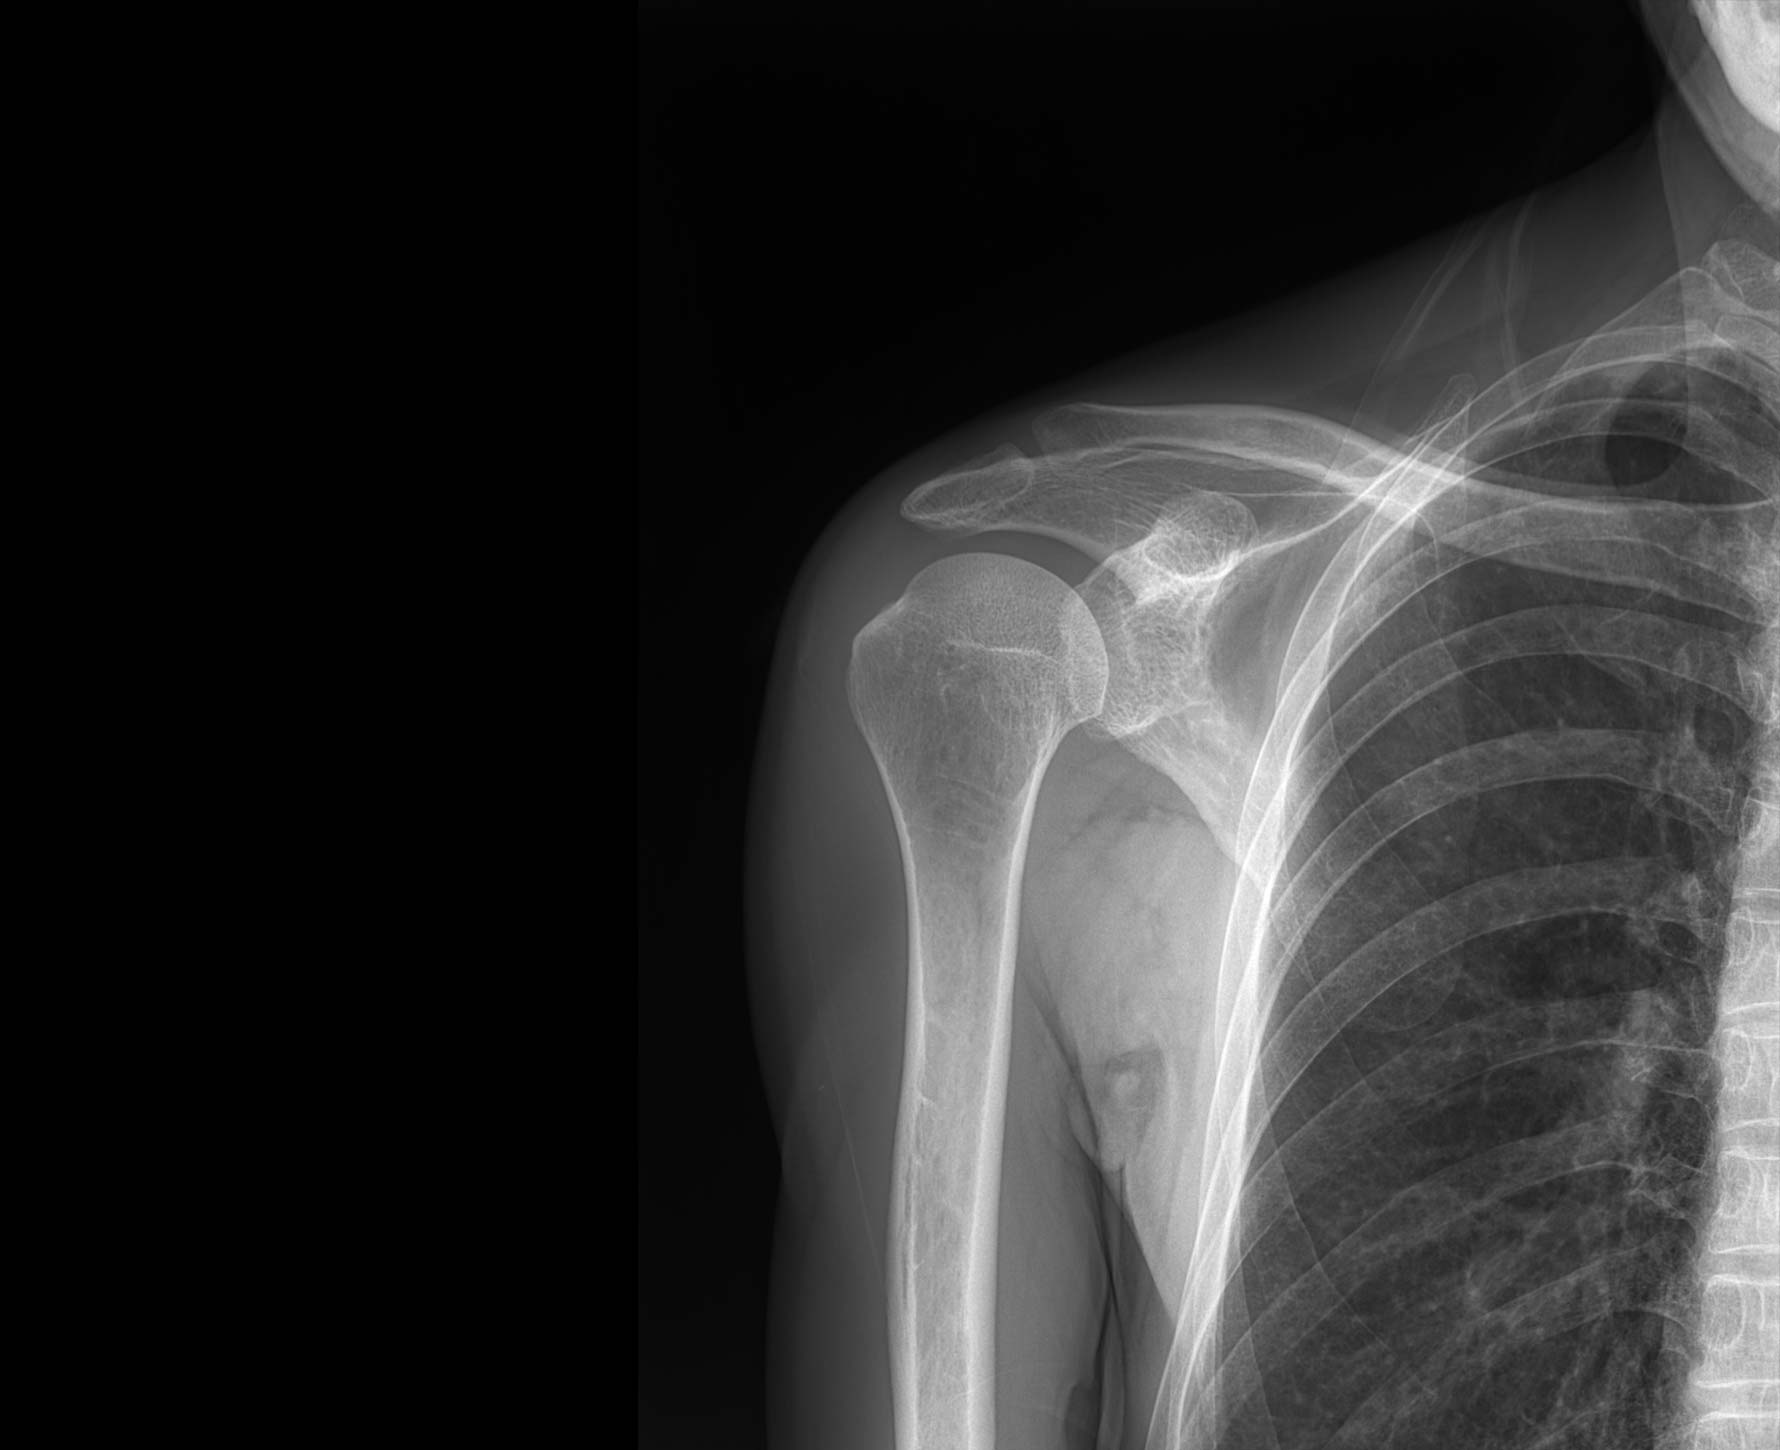

临床图像